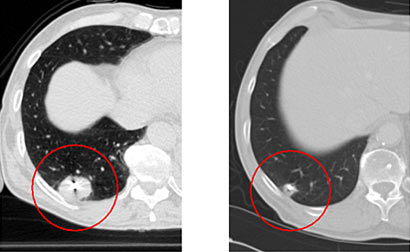

Das linke Bild zeigt eine Kernspintomograpie der Leber mit einer Metastase bei Darmkrebs. In der Mitte ist das entsprechende PET-CT, welches die biologische Aktivität des Tumors dargestellt. Das rechte Bild zeigt die Kernspintomograpie der Leber 8 Wochen nach einmaliger atemgesteuerter Präzisionsbestrahlung mit Cyberknife. Der Tumor ist ausgeschaltet (zentrale Nekrose) und es zeigt sich nur eine minimale Umgebungsreaktion.